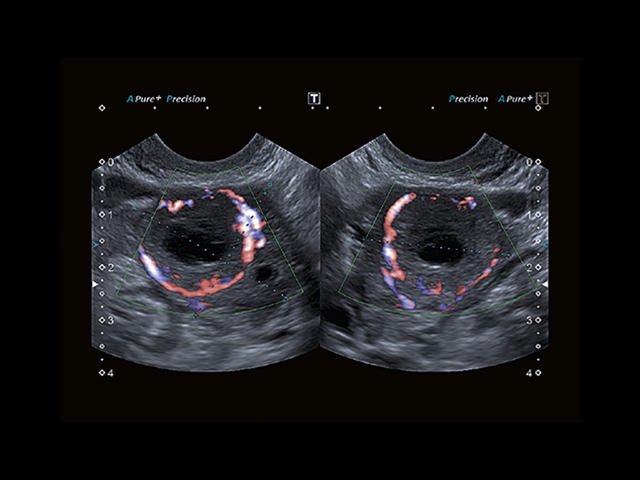

Обновленная версия легендарного УЗ-сканера. Стационарный аппарат экспертного класса Aplio 500 Toshiba NEW, визуализирует анатомические структуры в высоком разрешении. Модель позволяет выявить микрокальцификаты, новообразования, нарушения в работе сердца, сосудов и мышц. Присутствует функция виртуальной эндоскопии, 4D-сканирования, эластометрии тканей, УЗИ с контрастированием. За повышение качества изображения отвечают технологии ApliPure и Superb Microvascular Imaging. Первая задействует возможности пространственного и частотного кодирования, формирует цельный визуальный ряд с сохранением клинических маркеров. Вторая улучшает отображение микрососудистого русла, используя доплеровский эффект. Модель оснащена 21-дюймовым монитором, имеет 4 активных порта. Возможно подключение педиатрических, интраоперационных, лапароскопических и чреспищеводных датчиков.

• SMI. Опция, упрощающая визуализацию микроциркуляторного русла. С ее помощью обследуются сосуды с низкой интенсивностью кровотока, изучаются наиболее тонкие структуры. SMI упрощает диагностику новообразований, минимизирует вероятность ошибки.